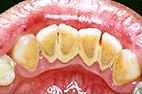

Zähne mit Zahnstein |

Kommen Sie zweimal jährlich

zum Zahnarzt - auch wenn gar nichts weh tut. Dann kann der

Zahnarzt die Zähne regelmäßig kontrollieren

und eventuell frühzeitig behandeln. Das verursacht nicht

nur weniger Schmerzen, sondern auch geringere Kosten.

Bei Ihren regelmäßigen Kontrollbesuchen in der

Praxis wird der entstandene Zahnstein entfernt. |